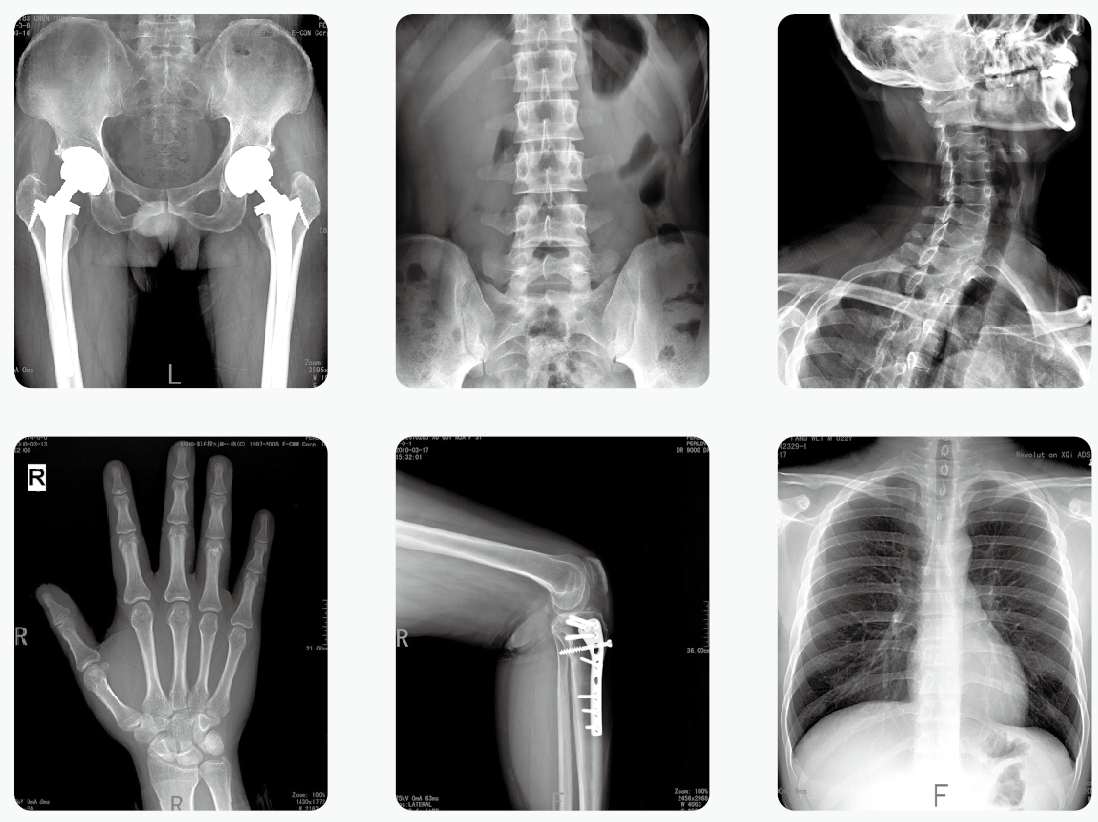

移动式DR为移动式X射线摄影医疗诊断设备,可用于放射科摄影、影像科摄影、儿科摄影、体检摄影、手术室及重症监护室摄影,满足对人体关节、骨骼、胸部、泌尿、妇科和特殊部位的X射线摄影要求。

【产品临床图片】